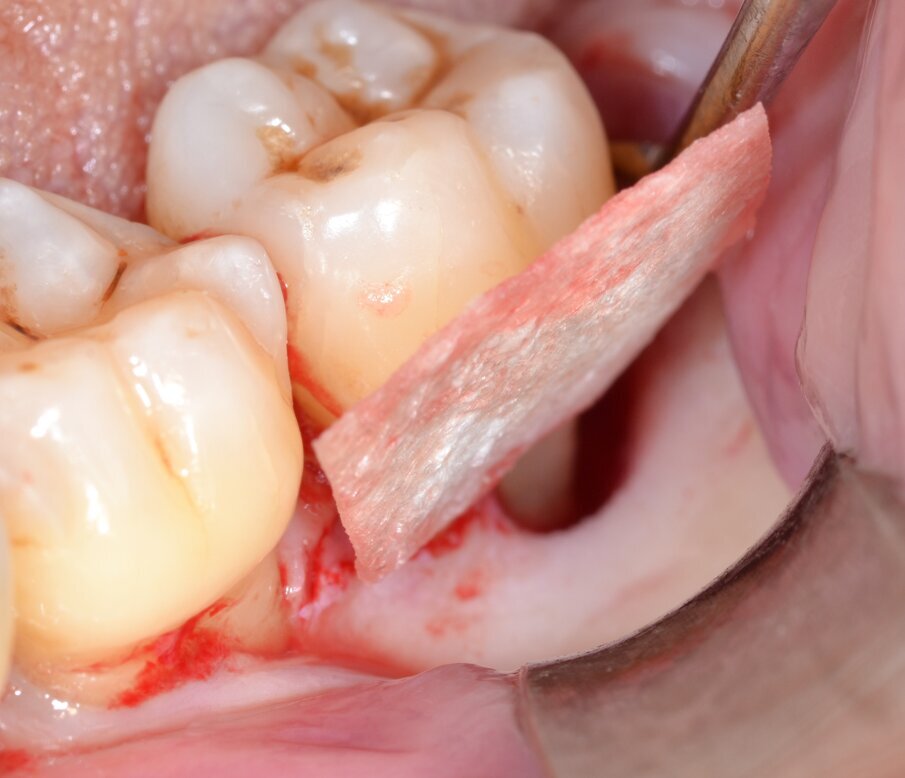

Dopo analgesia locale ottenuta per infiltrazione di Articaina cloridrato 40 mg con epinefrina 1:100.000 viene effettuata l’incisione di accesso secondo la tecnica denominata “Crestal Incision”4 per elevare un lembo a spessore totale che espone l’area interessata dal difetto (Fig. 5). Il debridement e la decontaminazione della superficie radicolare vengono effettuati per mezzo di inserti ultrasonici dedicati (Figg. 6, 7); al completamento di questo tempo chirurgico il difetto è innestato con biomateriale eterologo protetto da una membrana di tipo riassorbibile in pericardio di origine animale che viene fissata sulla cresta ossea mediante pins in titanio allo scopo di stabilizzare il coagulo e guidare la rigenerazione tissutale all’ interno del difetto. La ferita chirurgica è suturata con un filo riassorbibile 6/0 in PGA (Figg. 8-12).

Fig. 8 - Sagomatura della membrana riassorbibile in pericardio.

Fig. 9 - Allocazione della membrana barriera sull’aspetto linguale.

Fig. 12 - Sutura della ferita chirurgica con monofilamento 6/0.